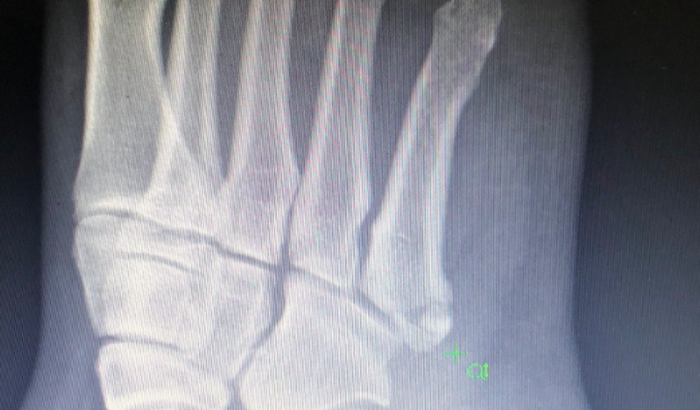

No final de abril sofri uma fratura “quebrou” o osso da base do quinto metatarso do meu dedinho.

Vou deixa a foto do meu Raio X.